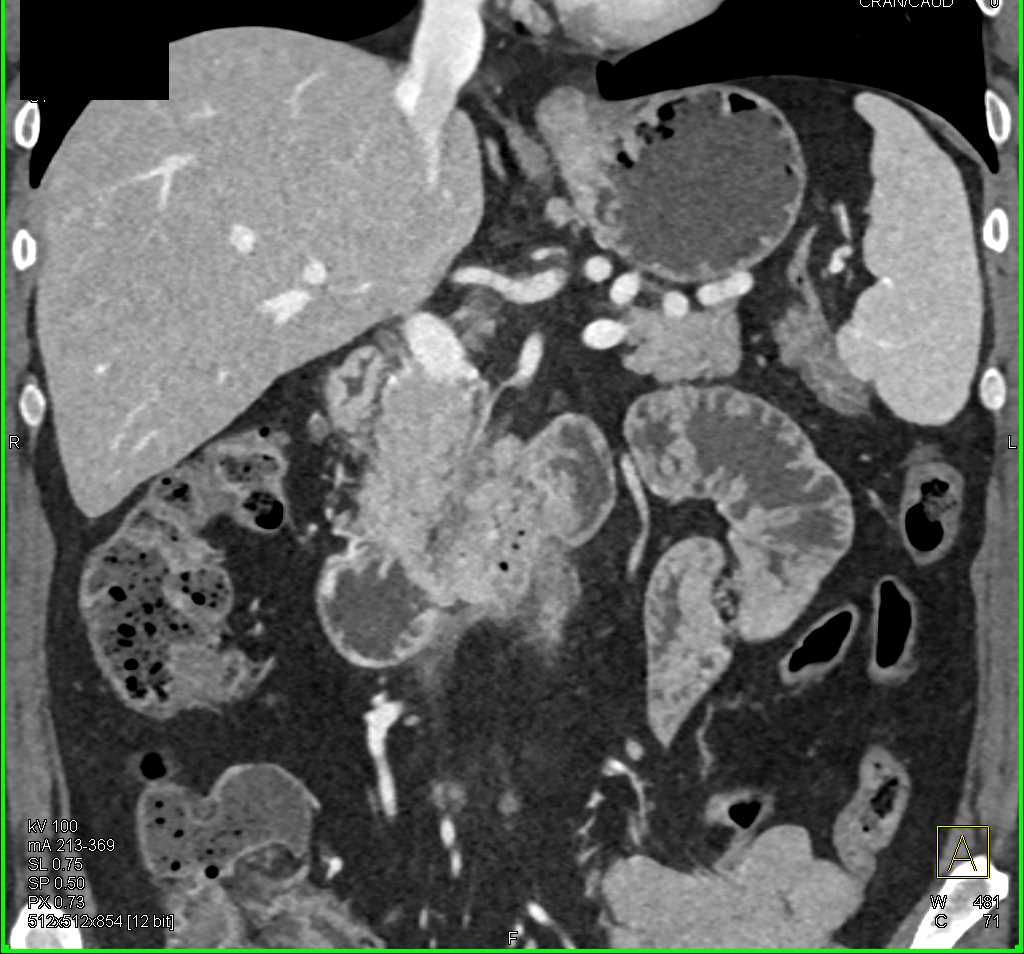

Duodenal Carcinoma with Obstruction